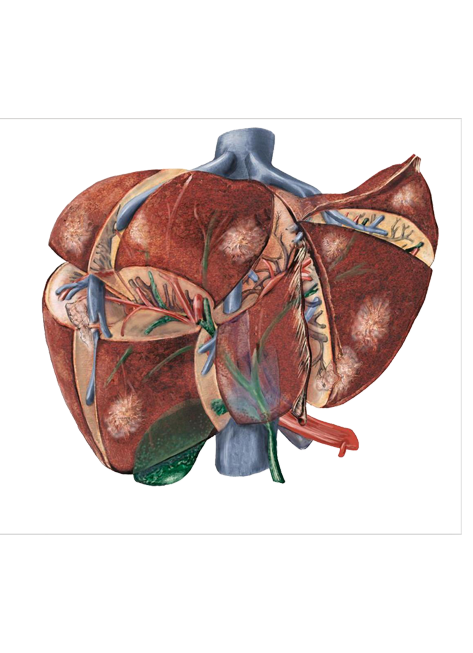

Leads one of the few African centres performing advanced laparoscopic Whipple procedures and major liver resections. Actively involved in research, training, and program development.

Liver tumours may be benign or malignant and malignant liver tumours may be primary (arising from liver) or secondary (metastatic).